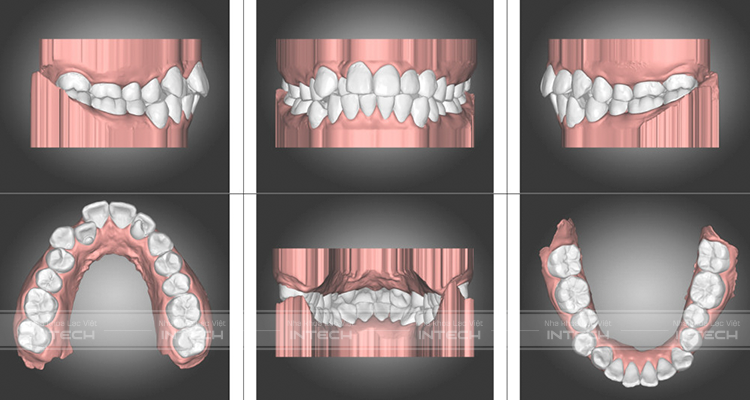

Nhờ phần mềm Auto lign của công nghệ niềng răng X- Matrix mà chúng ta có thể nhìn thấy kết quả sau niềng răng của bạn Trần Đức Khải.

• Toàn bộ răng hai hàm đã đều đẹp, nằm đúng vị trí trên cung hàm

• Đường giữa hai hàm trên dưới trùng nhau

• Đưa về khớp cắn chuẩn

• Răng cửa mọc đúng vị trí.

Mô phỏng kết quả niềng răng sau điều trị